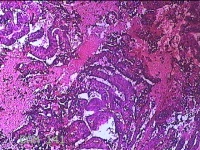

性别

女

年龄

34岁

临床诊断

异常子宫出血

一般病史

阴道不规则流血1月余。

标本名称

宫内物

大体所见

灰白暗红色不规则碎组织4.8x4.3x1.3cm一堆。